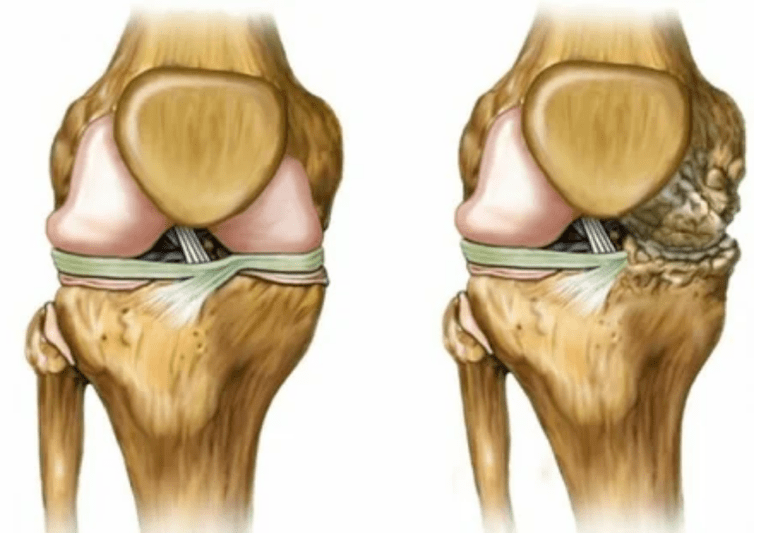

- 1 Grad. Morphologische Störungen haben bereits begonnen, sind aber noch nicht offensichtlich. Die Pathologie beeinflusst hauptsächlich den Zustand der Synovialflüssigkeit, wodurch die Knorpelgewebe mit Nährstoffkomponenten verschlechtert werden und die Stärke des Knorpels verringert. Die Last der Gelenke verursacht Entzündungen und Schmerzen.

- Phase 2 Die Schmerzen erwerben einen ausgeprägteren Charakter, der nach einer langen Pause verstärkt wurde, sie werden durch eine kleine körperliche Arbeit beseitigt. Der Schmerz wird von Entzündungen begleitet. Die Muskeln sind verlängert, was zu motorischen Funktionen mit schwachen oder mittleren Behinderungen führt.

- 3 Grad. Oft gibt es Schmerzen, es ist schwierig, das Glied aufgrund von Veränderungen im Gelenk zu bewegen. Die Läsionen werden erweitert, sie werden sich dem nackten Erscheinungsbild ersichtlich. Die Verformung der Gelenkstelle tritt auf, der betroffene Bereich schwillt an und wird rot. Die Achse des Gliedes wird gestört, was zur Komplexität der Bewegung führt. Pathologische Veränderungen verursachen die Verkürzung von Bändern. Subbules und Vertrag erscheinen. Die angrenzenden Muskeln werden abgekürzt oder verlängert, aus denen die kontraktile Funktion geschwächt wird.

Deformationen der Gliedmaßen. Es erscheint in einer vernachlässigten Form der Krankheit und zeigt die vollständige Zerstörung des Knorpelgewebes und das Auftreten von Osteophyten an. In diesem Zustand nimmt der Druck auf die Gelenke im oberen und unteren Teil zu, aus dem die Krümmung das gesamte Glied beeinflussen kann.